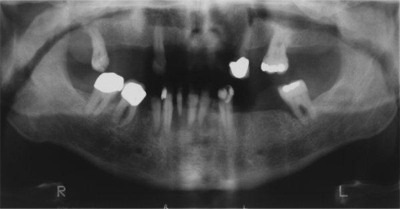

An orthopantomogram revealed generalized bone loss especially in the lower anterior region consistent with advanced periodontitis. There was no evidence of intraosseous pathology (Fig. 2).

Figure 2: Orthopantomogram showing generalized bone loss with no obvious intraosseous pathology.